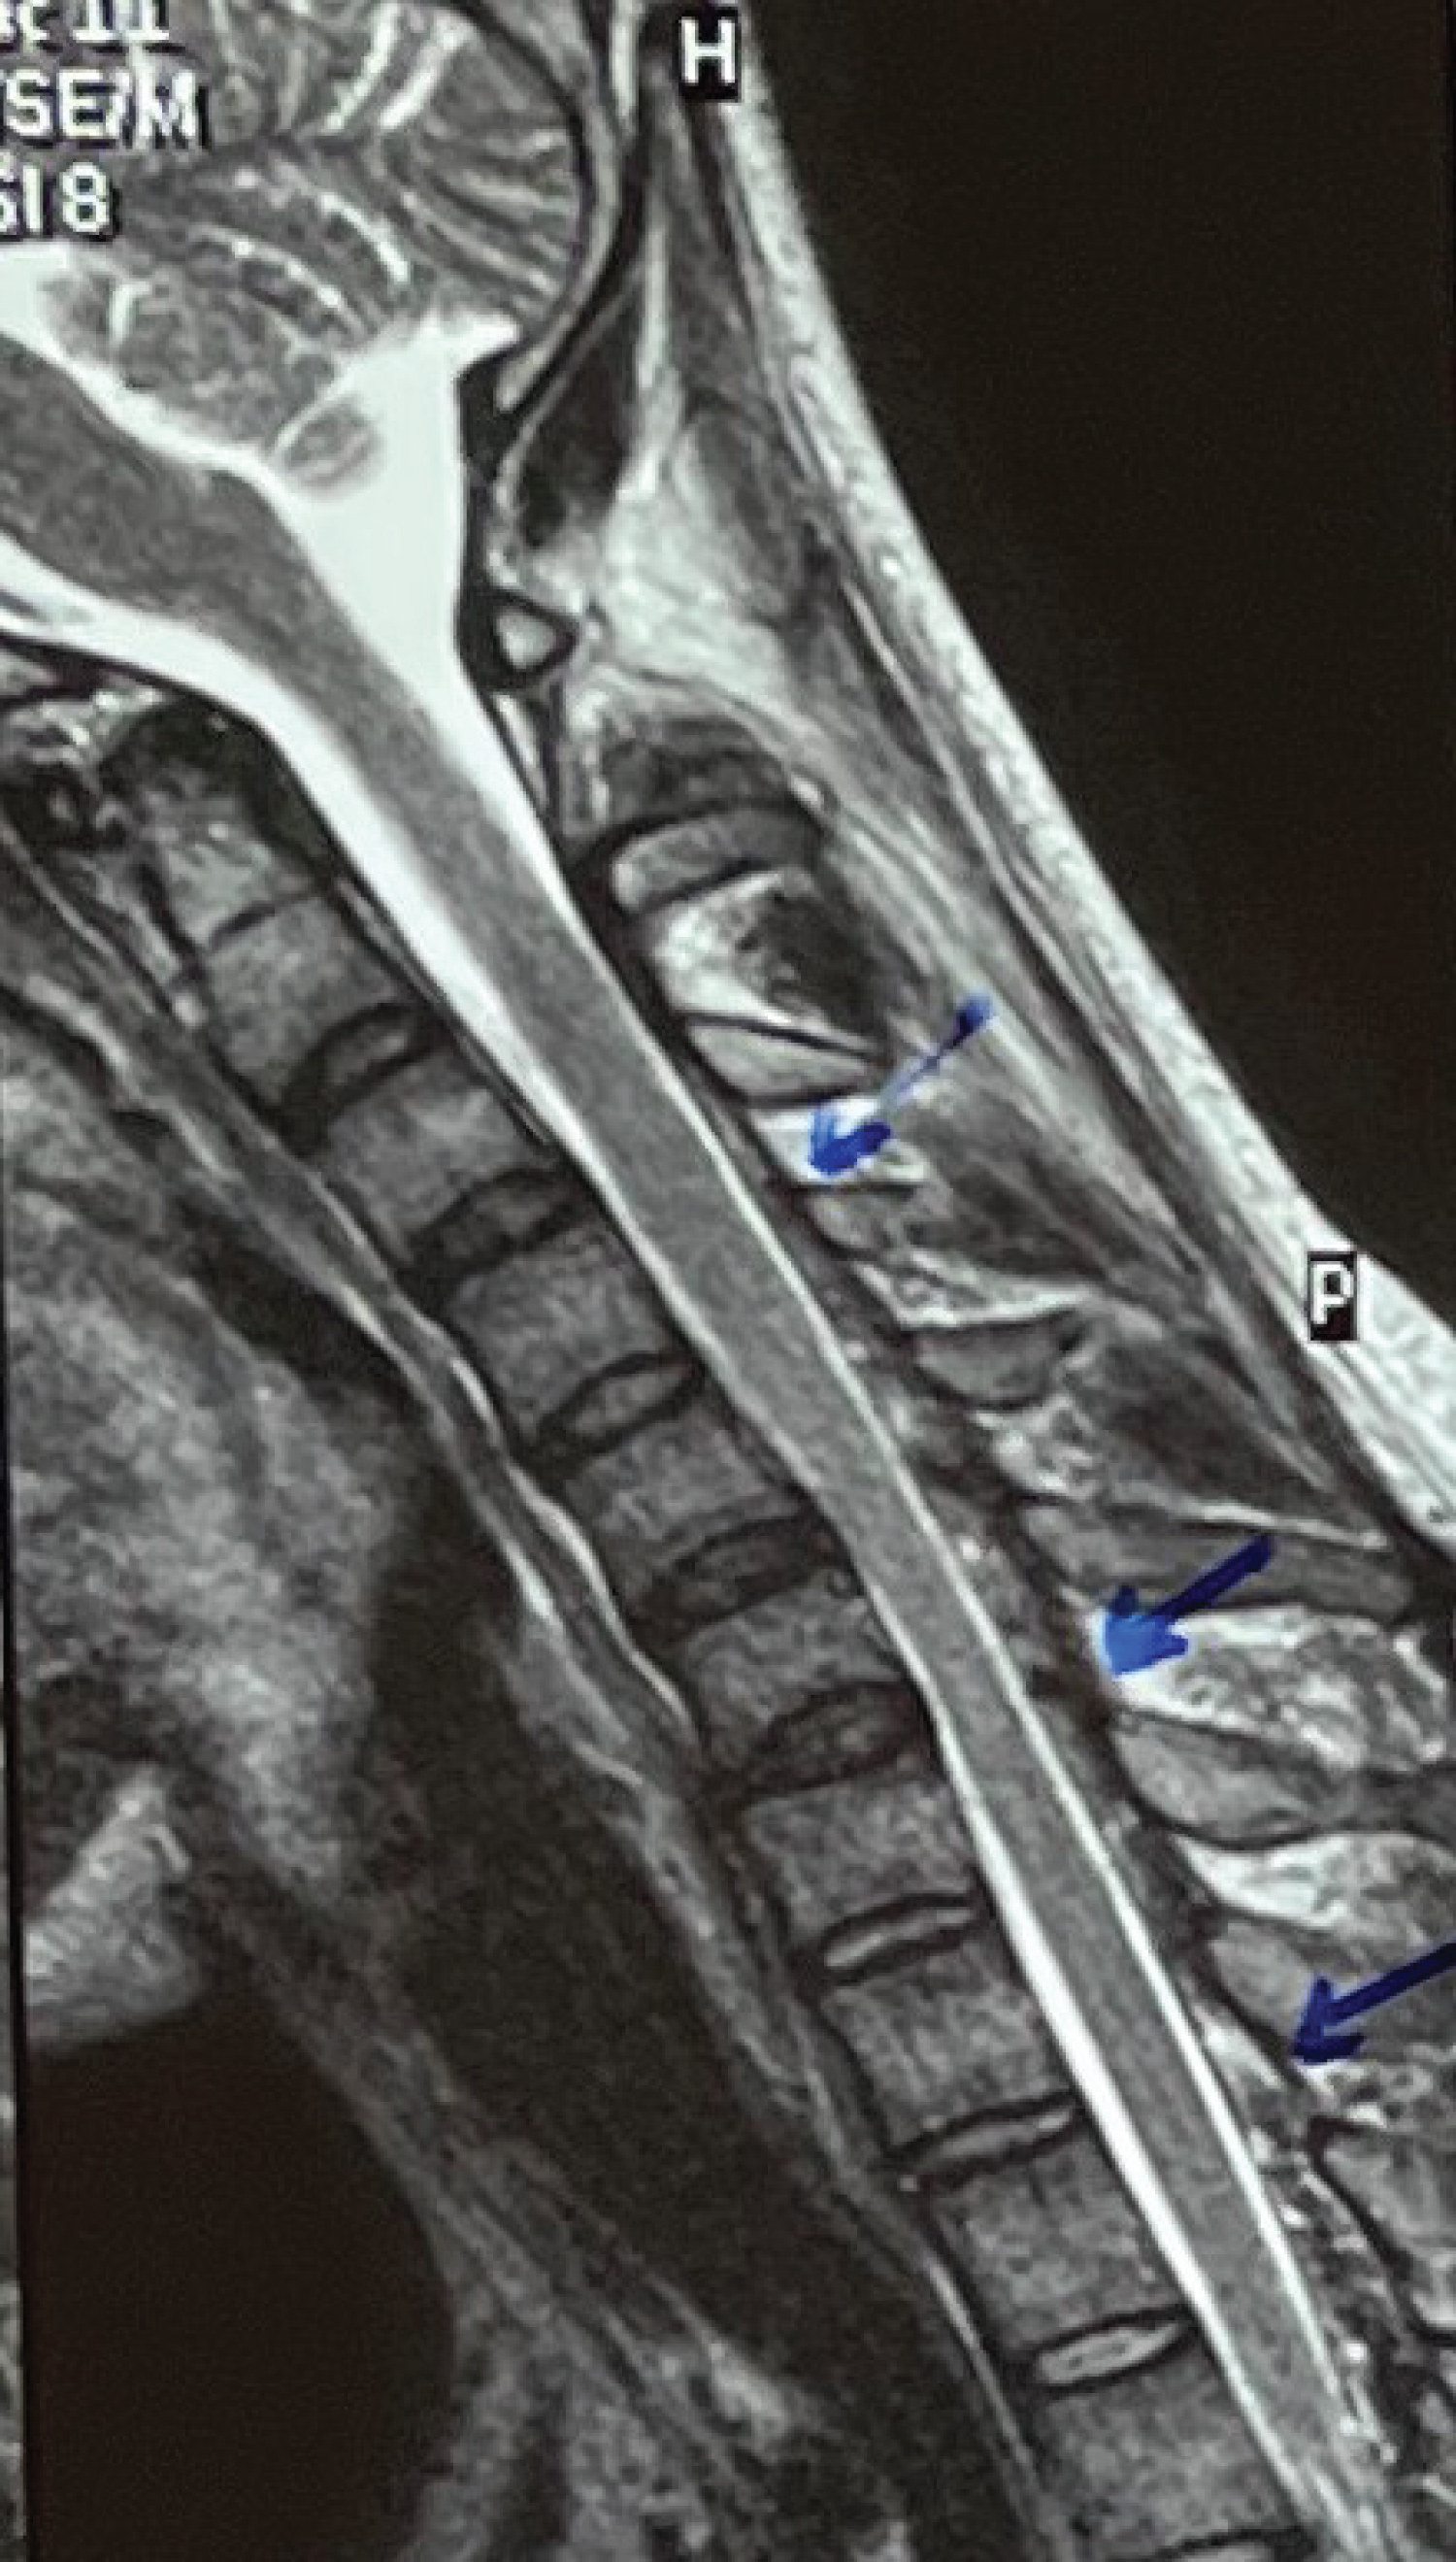

A twenty-one-year-old male right-handed came to us with a chief complaint of weakness in the grip of both hands (right > left) which was noticed by him in August 2020 when he was gathering clay with his bare hands to make a Ganesha idol. He experienced that this weakness was static and non-progressive and was not related to any aggravating or relieving factors. The patient also had a history of occasional tingling in both of his hands since childhood which was left unattended. The patient started noticing the loss of the bulk of his bilateral hand muscles. The patient did not have weakness in proximal upper limbs or any of the lower limbs. He did not have any complaints regarding bowel and bladder habits. On examination, we found wasting of thenar as well as hypothenar muscles (Figure 1 and Figure 2). The patient had asymmetric weakness in all his intrinsic muscles (3/5) of both hands. All the sensations were well preserved and deep tendon reflexes were normal. The nerve conduction studies, and EMG findings were suggestive of bilateral C8-T1>>C7>>C5-C6 very chronic motor axon degeneration with the site of involvement likely to be at anterior horn cell or cord level. His MRI of the cervical spine (Figure 3, Figure 4 and Figure 5) was showing focal atrophy of the lower cervical spinal cord from C5-C6 to C6-C7 disc levels with mild prominence of the central canal and on flexion, there was the ventral movement of posterior dura with the prominence of the posterior epidural venous plexi extending from C3 to upper dorsal levels. All these findings were suggestive of Hirayama disease. The patient was advised to wear a cervical collar and on follow up after two months he had relief from his tingling and there was an improvement in power (4/5) of intrinsic muscles of both hands. He was able to write in reasonably good handwriting and was able to perform all his routine activities without any disturbances.

Figure 3: Sagittal T2 image in neutral position showing cord atrophy at C5, C6, C7 level with mild prominence of the central canal. View Figure 3